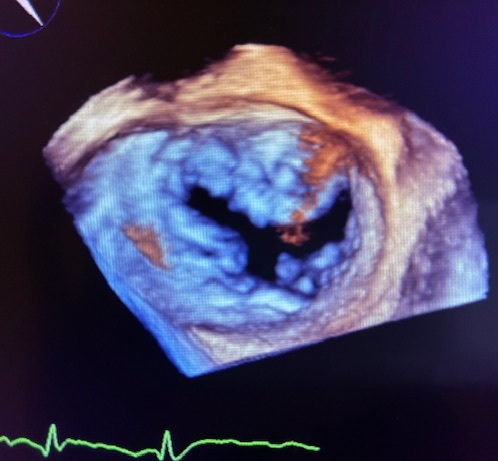

・超音波検査について(臨床検査室)